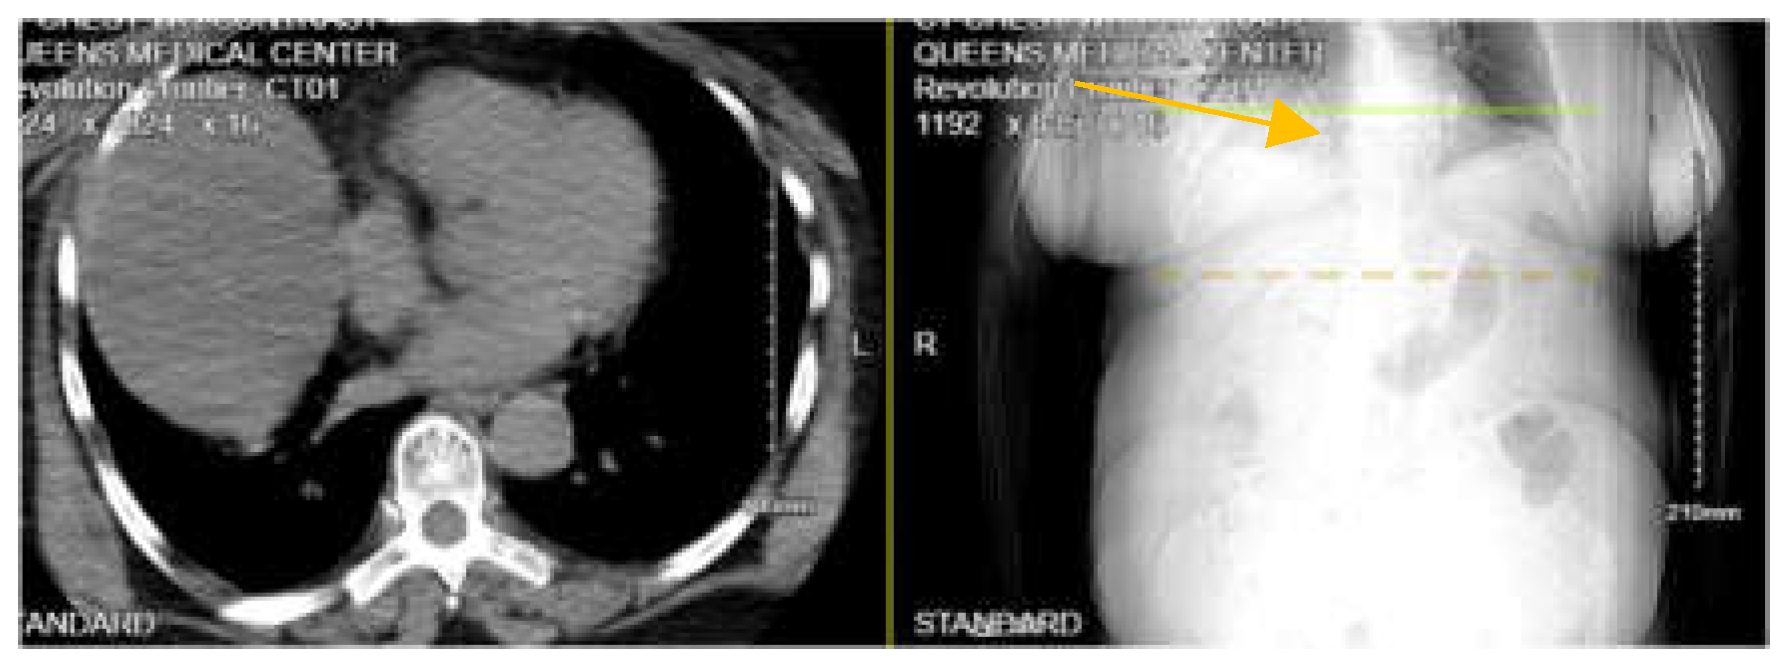

A 74-year-old Hispanic female with a past medical history of diabetes mellitus and hyperlipidemia presents to the ED as a transfer from another facility with a complaint of right-sided rib cage pain and right arm pain. According to the patient, she fell earlier today at home. The patient reported falling 7-8 steps while walking up the stairs in her home. She mentioned feeling dizzy before falling and hitting the right side of her body. Denied head trauma or loss of consciousness. Her vitals were stable in the ED with a BP of 140/88 mmHg. On examination, there was tenderness on the chest wall and right upper arm, abrasions, and bruising to the right side of the rib cage. CT chest without contrast (Figure 5) showed acute displaced lateral right 7th and 8th rib fractures and comminuted scapular fractures. Moderate right hemidiaphragm elevation. The patient underwent exploratory laparoscopy, and no diaphragmatic injury was identified. ISS 9.

Figure 5. CT chest without contrast showing moderate right hemidiaphragm elevation.